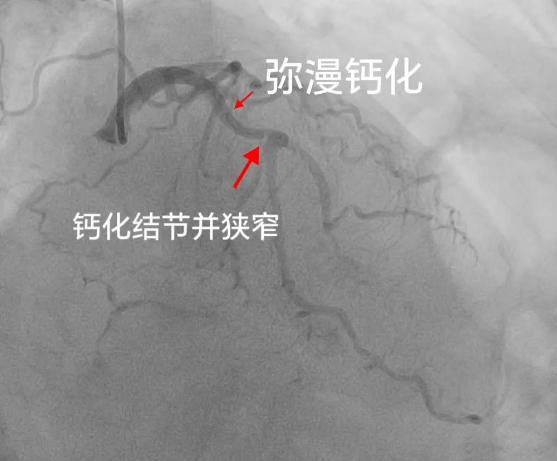

患者王老太,今年72岁,因反复胸闷、胸痛到星城医院心内科就诊,住院后,行冠脉造影检查发现老太太心脏三根血管均有病变,其中右冠状动脉完全闭塞,左前降支严重钙化、迂曲并重度狭窄,考虑到患者年龄大,并伴有高血压、糖尿病等基础性疾病,而且血管钙化病变非常严重,如果是行常规介入治疗,支架恐怕难以通过,强行送入支架容易引起支架脱载、血管破裂等严重的并发症。

消毒、穿刺、送入导管,按照制定的程序一步步紧张而有序地进行,通过检查发现,老太太左前降支血管存在360度钙化,使用震波球囊对钙化病变多次治疗,钙化环充分断裂,经球囊扩张效果明显,随后,顺利植入支架。原本被“石头”堵塞的血管重新被扩张,恢复了血流,王老太的“心头”难题得以解决。